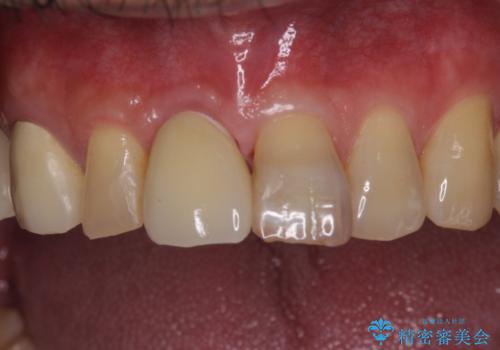

折れてしまった前歯 インプラントによる補綴治療